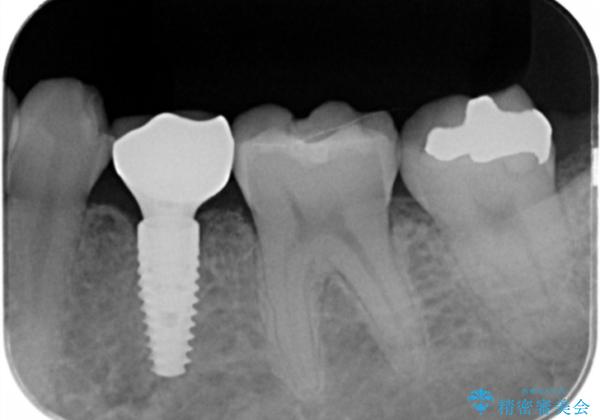

乳歯の残存 インプラントによる置き換え

- 大人になっても残存していた乳歯がグラグラし、痛くて噛めない 抜いて欲しいとの希望で来院されました。

歯根が吸収し残すことのできない乳歯を抜去後、隣の歯を削らずに済むインプラント治療で咬合機能の回復を計画します。

乳歯の抜去後、インプラントを用いてしっかりと咬合機能を回復することができました。